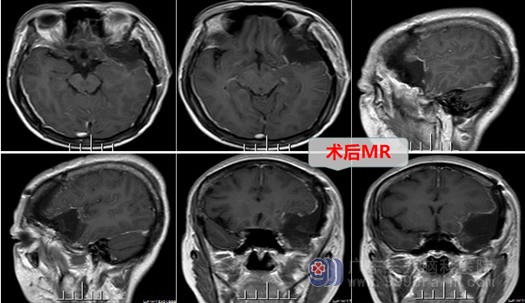

邱阿姨顺利的入住到三九脑科医院外十科,主治医师是邓心情医生,经过详细询问病史,专科的检查,结合患者的症状、体征,明确诊断为:左侧蝶骨嵴脑膜瘤,这是一个血供丰富、切除难度较大的良性肿瘤。外十科团队在欧阳主任带领下,最后制定完整的治疗方案,在征得邱阿姨及家属的同意后,择期行“左侧蝶骨嵴脑膜瘤切除术”,手术进行得顺利,肿瘤被完全切除,出血量很少,神经功能被良好保护。术后邱阿姨恢复很好,她高兴地说道:”感谢你们为我解决了这6年多的头痛,哎…这头痛还真的不能忽视,我以为平日偶尔头痛一下不是个问题,没想到脑袋还长瘤子了,幸好遇到优秀的医生、护士团队,感谢你们给我一次重生的机会!”